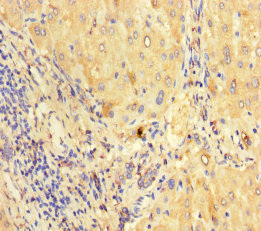

Immunohistochemistry of paraffin-embedded human liver tissue using CSB-PA05034A0Rb at dilution of 1:100